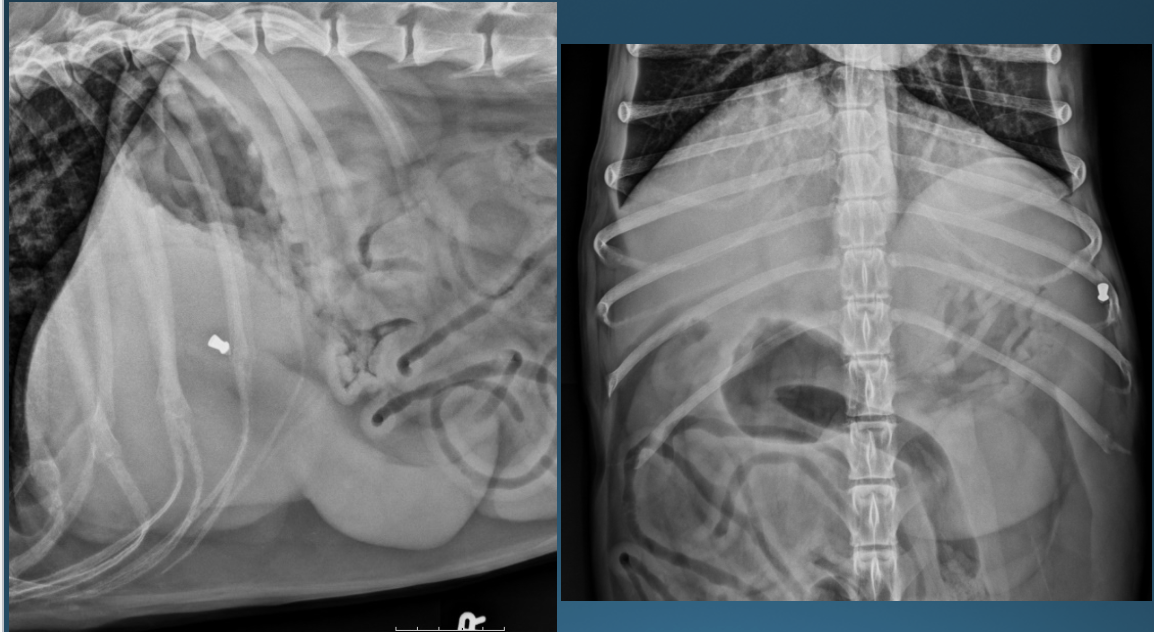

What is shown in these images?

*generalized hepatomegaly:

-hepatic congestion and ascites

-enlargement of hepatic vein and caudal vena cava